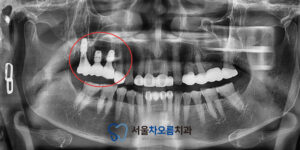

위 환자분은 오른쪽 위쪽 어금니 부위에

소구치부터 대구치까지 연결된

브릿지를 사용 중이셨는데,

브릿지가 흔들리면서 음식을 씹을 때

불편함을 느끼셨다고 합니다.

진단을 위해 파노라마 사진을 촬영한 결과,

다행히 앞쪽 치아인 작은 어금니는

치아 뿌리 상태가 양호했지만,

뒷쪽 큰 어금니는 흔들림이 심한 상태였습니다.

이에 기존 브릿지를 컷팅하여

작은 어금니 크라운은 유지하고,

뒷쪽에 해당하는 큰어금니는

흔들림이 심해 발치를 결정하였습니다.

그와 함께 중간 치아인 뒷쪽 작은 어금니와

앞쪽 큰 어금니까지 총 세 부위에

임플란트를 식립하기로 계획을 세웠습니다.